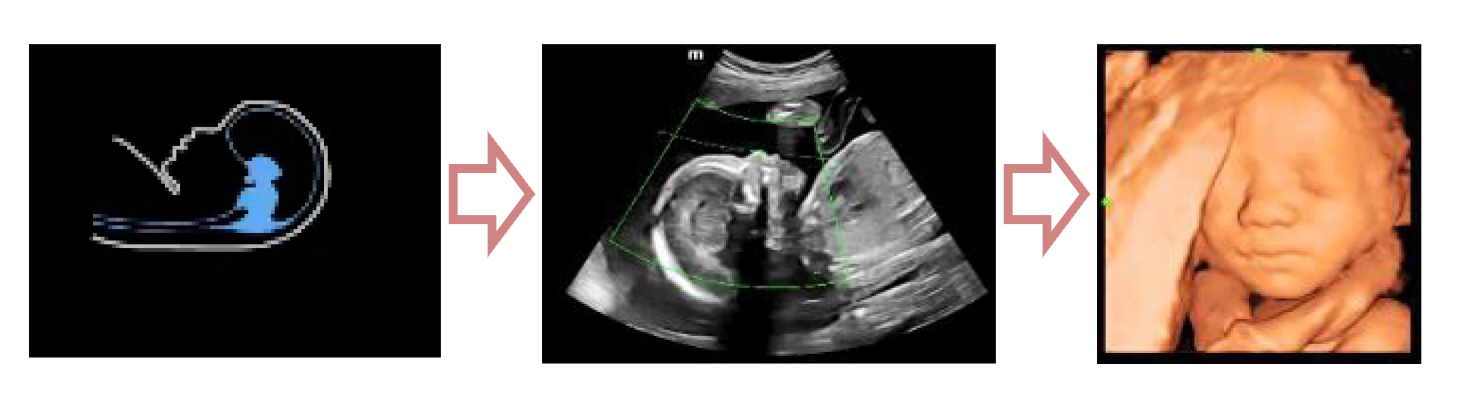

С легкостью получайте потрясающие объемные изображения лица плода.

- Автоматическое распознавание лица плода

- Автоматическая подстройка зоны интереса и положения до оптимального

- Автоматический определение параметров рендеринга лица плода